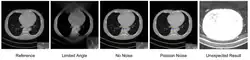

The influence of Poisson noise in deep learning reconstruction where Poisson noise causes the U-Net fail to reconstruct an existing high contrast lesion-like object.

Deep learning methods are widely applied to image reconstruction nowadays and have achieved impressive results in various image reconstruction tasks, including low-dose denoising, sparse-view reconstruction, limited angle tomography and metal artifact reduction. An excellent overview can be found in the special issue [5] of IEEE Transaction on Medical Imaging. One group of deep learning reconstruction algorithms apply post-processing neural networks to achieve image-to-image reconstruction, where input images are reconstructed by conventional reconstruction methods. Artifact reduction using the U-Net in limited angle tomography is such an example application.[6] However, incorrect structures may occur in an image reconstructed by such a completely data-driven method,[7] as displayed in the figure. Therefore, integration of known operators into the architecture design of neural networks appears beneficial, as described in the concept of precision learning.[8] For example, direct image reconstruction from projection data can be learnt from the framework of filtered back-projection.[9] Another example is to build neural networks by unrolling iterative reconstruction algorithms.[10] Except for precision learning, using conventional reconstruction methods with deep learning reconstruction prior [11] is also an alternative approach to improve the image quality of deep learning reconstruction.